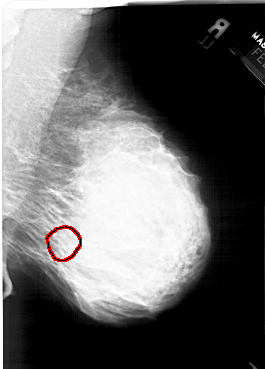

ics_version 1.0 filename A-1564-1 DATE_OF_STUDY 6 2 1996 PATIENT_AGE 43 FILM FILM_TYPE REGULAR DENSITY 4 DATE_DIGITIZED 14 9 1998 DIGITIZER HOWTEK 43.5 SEQUENCE LEFT_CC LINES 6331 PIXELS_PER_LINE 4156 BITS_PER_PIXEL 12 RESOLUTION 43.5 NON_OVERLAY LEFT_MLO LINES 5941 PIXELS_PER_LINE 4321 BITS_PER_PIXEL 12 RESOLUTION 43.5 NON_OVERLAY RIGHT_CC LINES 6226 PIXELS_PER_LINE 4261 BITS_PER_PIXEL 12 RESOLUTION 43.5 OVERLAY RIGHT_MLO LINES 6271 PIXELS_PER_LINE 4501 BITS_PER_PIXEL 12 RESOLUTION 43.5 OVERLAY |

FILE: A_1564_1.RIGHT_MLO.OVERLAY TOTAL_ABNORMALITIES 1 ABNORMALITY 1 LESION_TYPE CALCIFICATION TYPE PLEOMORPHIC DISTRIBUTION SEGMENTAL ASSESSMENT 4 SUBTLETY 4 PATHOLOGY BENIGN TOTAL_OUTLINES 1 BOUNDARY |